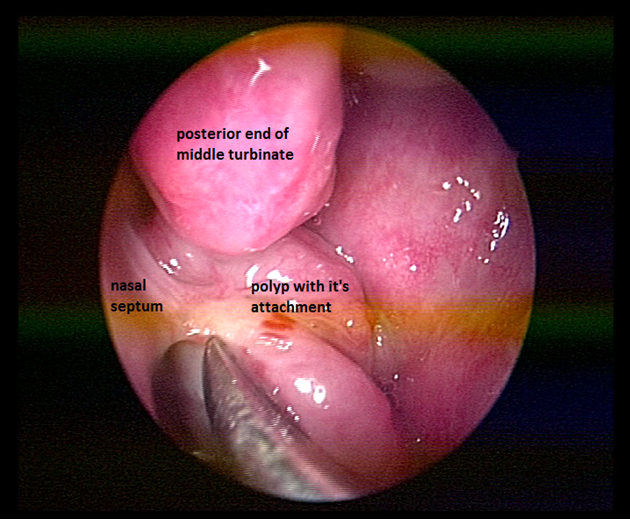

A 25year old man presented with history of progressive bilateral nasal obstruction and snoring for the past two years. There was no history of nasal discharge, post nasal drip, nasal bleeding and his wife reported difficulty in sleeping in the same room with the patient due to snoring. Anterior rhinoscopy was normal. On diagnostic nasal endoscopy a lobulated mass arising from the superior aspect of posterior septum on left side, obstructing whole of the choana was seen (Figure 1). Computed tomography revealed a soft tissue mass occupying whole of the nasopharynx abutting the nasal septum (Figure 2). Paranasal sinuses were normal. Patient was taken up for endoscopic excision and biopsy. Local anesthesia was infiltrated in the pedicle and the stalk of the polyp was resected with the small amount of normal surrounding mucosa. The base of the stalk was cauterized with bipolar cautery. No nasal packing was required and patient was discharged on the same day. Macroscopically the mass was of around 5X2X2cm with lobulated surface and multiple firm nodules were palpable over the surface (Figure 3). On cut section white strands were found, along with few cystic areas (Figure 4). Histopathology revealed a polypoidal tissue mass with marked inflammatory infiltrate containing mostly lymphocytes with lack of Stromal edema and goblet cell hyperplasia; these were suggestive of fibroinflammatory polyp. Postoperative period was uneventful. There was no recurrence in the six months follow up.

Figure 2 CT scan showing the polyp present in nasopharynx abutting the nasal septum. Sinuses are clear.